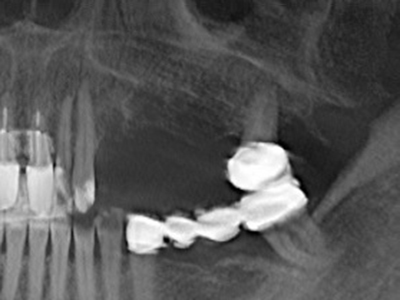

El tejido óseo no solo tiene un contenido puramente mineral, sino que también presenta una importante proporción de fibras de colágeno. Esto no solo garantiza una buena resistencia a la presión, sino también una cierta flexibilidad, que puede aprovecharse para la realización de aumentos. En la plastia de expansión clásica a efectos de una partición ósea, la cresta maxilar atrofiada se divide en su eje longitudinal y, tras alcanzar una profundidad de osteotomía suficiente, se extiende con cuidado (fig. 13-16), en un caso ideal sin desperiostizar de forma visible el maxilar (Brugnami, Caiazzo et al. 2014, Stricker, Fleiner et al. 2014). Los sistemas de tornillos y placas con distancia de expansión creciente han demostrado su eficacia para distanciar entre sí las dos tablas óseas por debajo del umbral de rotura. Por regla general, se requieren anchuras de hueso residual de al menos 3 a 4 mm (Chiapasco, Zaniboni et al. 2006) para garantizar una flexibilidad y una cobertura ósea suficientes de los implantes que van a incorporarse. En caso necesario, una osteotomía de descarga vertical unilateral o bilateral puede mejorar la flexibilidad. Como alternativa a la técnica clásica se ha descrito una combinación con otras técnicas de aumento, sobre todo en la parte bucal.

Con el uso de sierras piezoeléctricas la división se efectúa de forma especialmente cuidadosa y sin pérdidas importantes de las dimensiones, por lo que no se han encontrado diferencias significativas entre los implantes realizados en el maxilar dividido y en la cresta alveolar no deficitaria (Chiapasco, Zaniboni et al. 2006, Danza, Guidi et al. 2009). No obstante, precisamente en la partición profunda y limitada de forma local, es preciso asegurarse de que exista una adecuada irrigación por agua para evitar que se produzcan sobrecargas térmicas en las áreas de osteotomía apical.